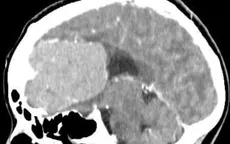

Vi phẫu nền sọ lấy khối u não "khổng lồ" cho bệnh nhân nữ VTV.vn - Bệnh viện Đa khoa Thái Bình (Hưng Yên) vừa phẫu thuật thành công khối u não kích thước lớn tại vùng trước nền sọ cho một bệnh nhân nữ.